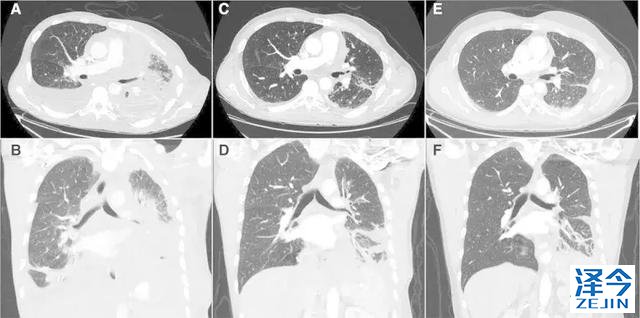

一位77岁的女性患有EPS15-NTRK1 IV期非小细胞肺癌,我们可以看到她的双肺满是病灶,并且出现了肝脏和脑转移,可以说是非常非常晚期了,

肺靶病变达到缓解,我们可以明显的看到前后的图像,病灶明显缩小了,

脑转移病变显示缩小了95%!

初始, 2018年6月 3周期 2018年8月